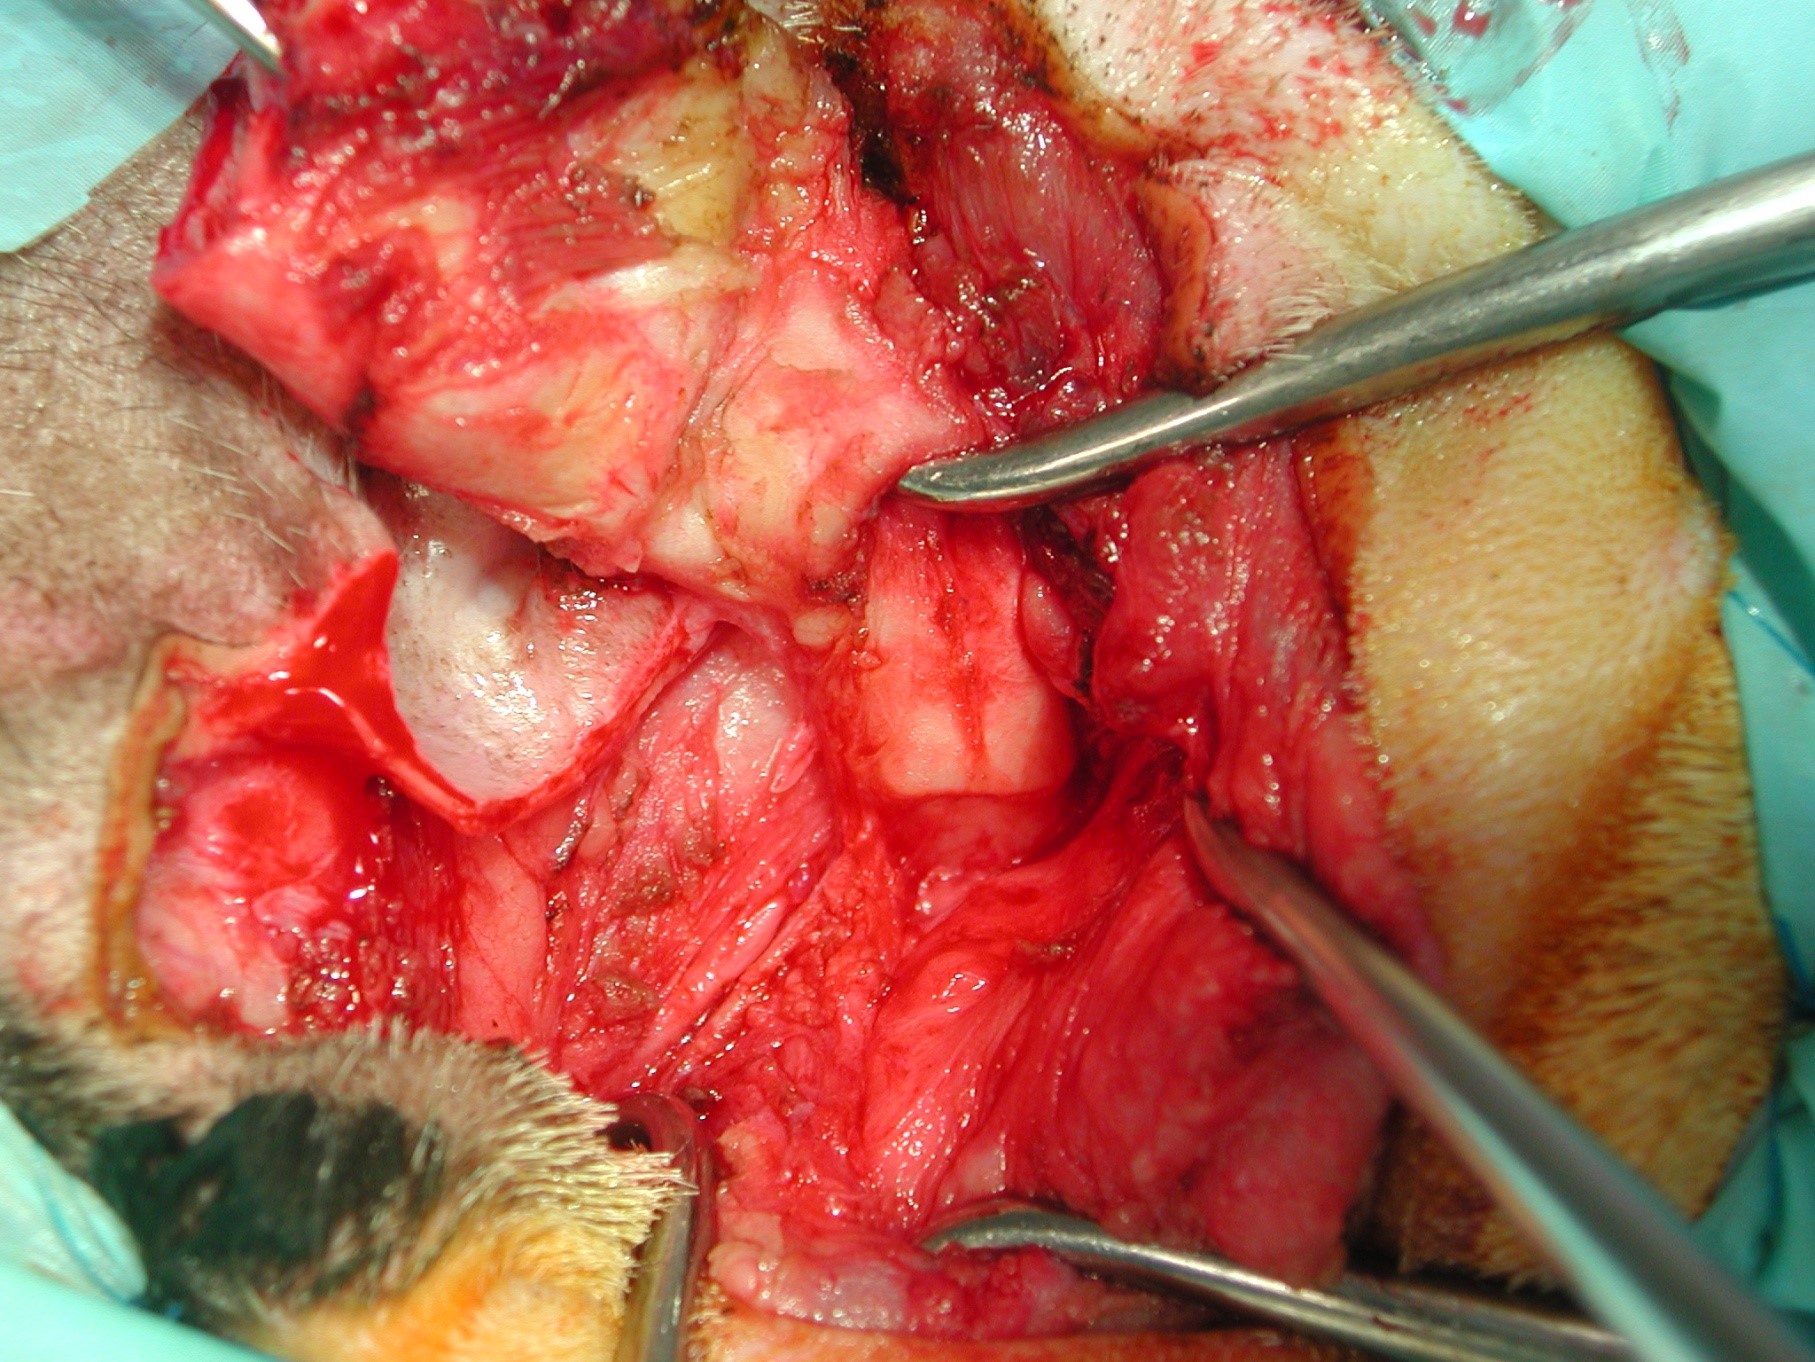

-Les étapes de la bullotomie ventrale (VBO) chez le chat en photo et vidéos

-VBO : comment la réaliser en pratique.